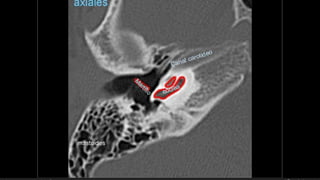

Evaluación Imagenologica

• #38 Izqu. AXIAL-- fxLongitudinal perdonan la capsula otica (laberinto oseo) Centro AXIAL fx trnasversa lascuales tperdonan el lab erinto oseo Dere: MIXTA – tmp perdona

Hipoacusia  Conductiva 26-57% -- longitudinal – lesión osicular, MT, Hemotimpano  Sensorial  14-23% -- transversa -- OCV  Mixta  20-55%  Dislocacion incudoestapedial  57-80%  Dislocacion incudomaleolar 51%  Fractura estapedio  30%  Fractura martillo  8%